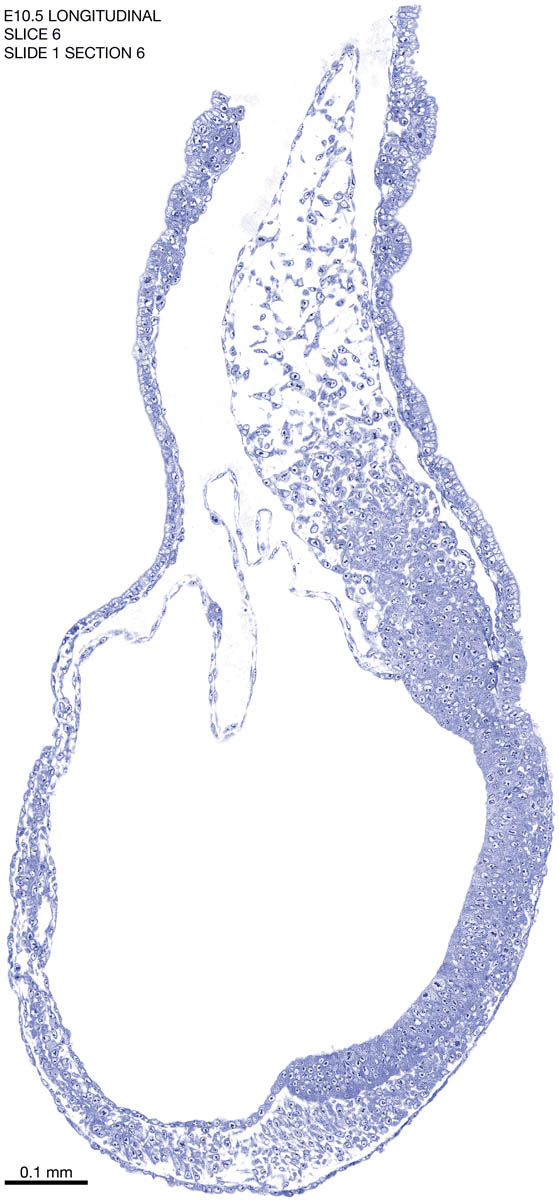

E10.5 Longitudianal Archive This page contains jpg files of ALL SLICES (each 3µm thick) that were scanned of the E10.5 longitudinally cut specimen. Download: Large | High Res Download: Large | High Res Download: Large | High Res Download: Large | High Res Download: Large | High Res Download: Large | High Res Download: Large | High Res Download: Large | High Res Download: Large | High Res Download: Large | High Res Download: Large | High Res Download: Large | High Res Download: Large | High Res Download: Large | High Res Download: Large | High Res Download: Large | High Res Download: Large | High Res Download: Large | High Res Download: Large | High Res Download: Large | High Res Download: Large | High Res Download: Large | High Res Download: Large | High Res Download: Large | High Res Download: Large | High Res Download: Large | High Res Download: Large | High Res Download: Large | High Res Download: Large | High Res Download: Large | High Res Download: Large | High Res Download: Large | High Res Download: Large | High Res Download: Large | High Res Download: Large | High Res Download: Large | High Res Download: Large | High Res Download: Large | High Res Download: Large | High Res Download: Large | High Res Download: Large | High Res Download: Large | High Res Download: Large | High Res Download: Large | High Res Download: Large | High Res Download: Large | High Res Download: Large | High Res Download: Large | High Res Download: Large | High Res Download: Large | High Res Download: Large | High Res Download: Large | High Res Download: Large | High Res Download: Large | High Res Download: Large | High Res Download: Large | High Res Download: Large | High Res Download: Large | High Res